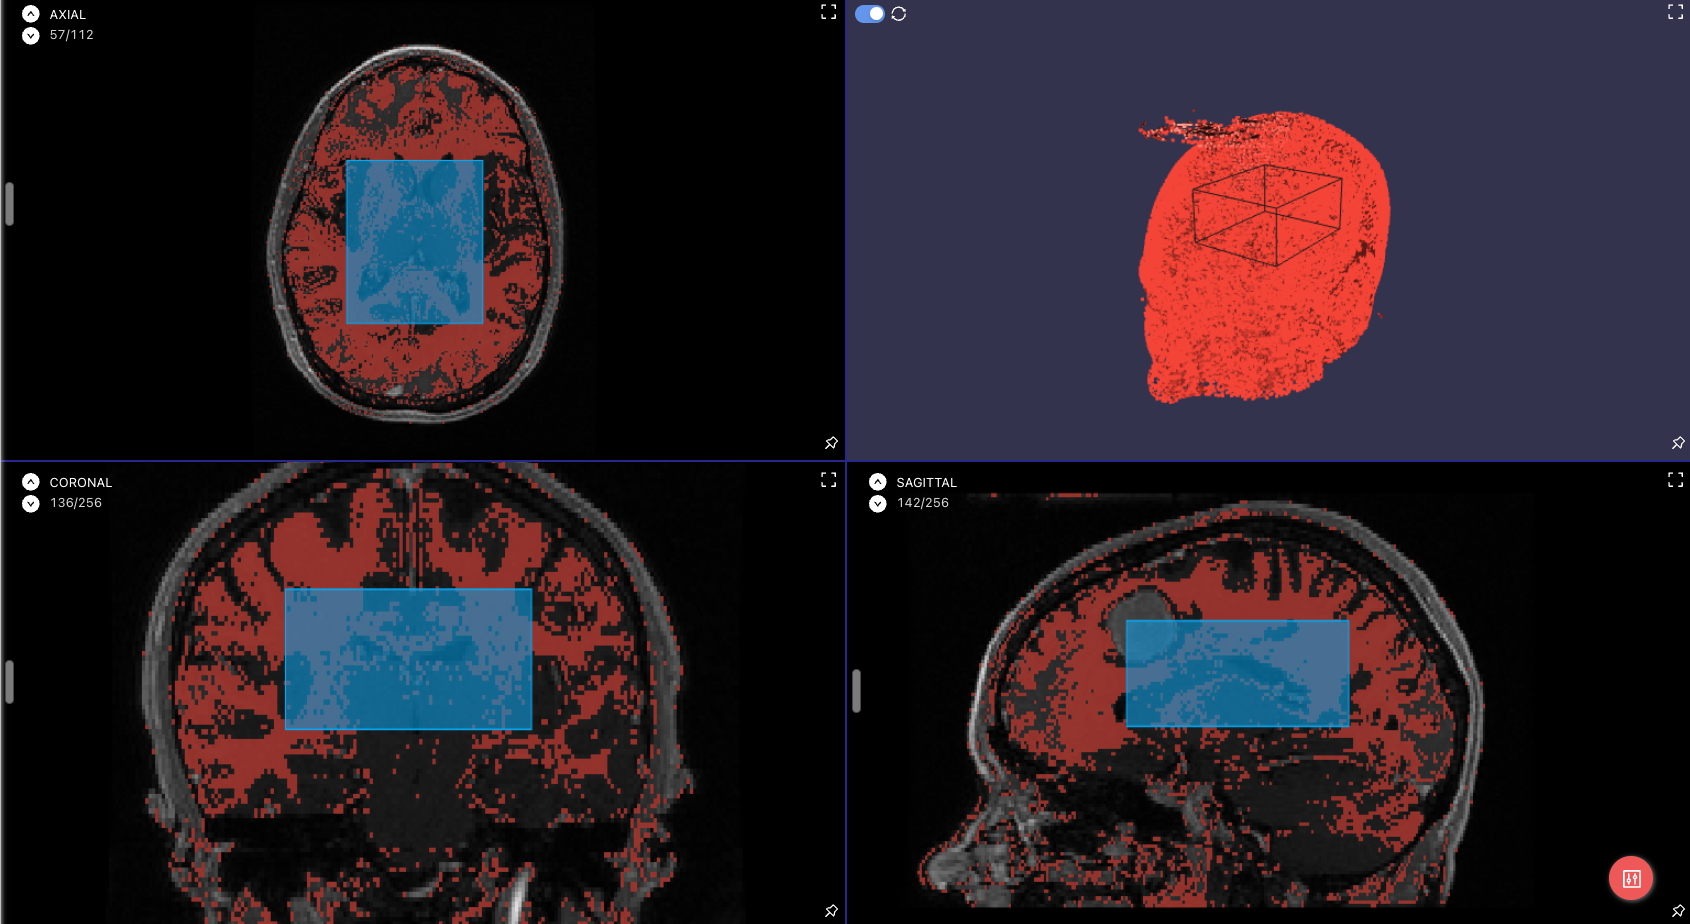

3D Bounding Boxes are now available in the medical labeling editor. Read more in our docs.